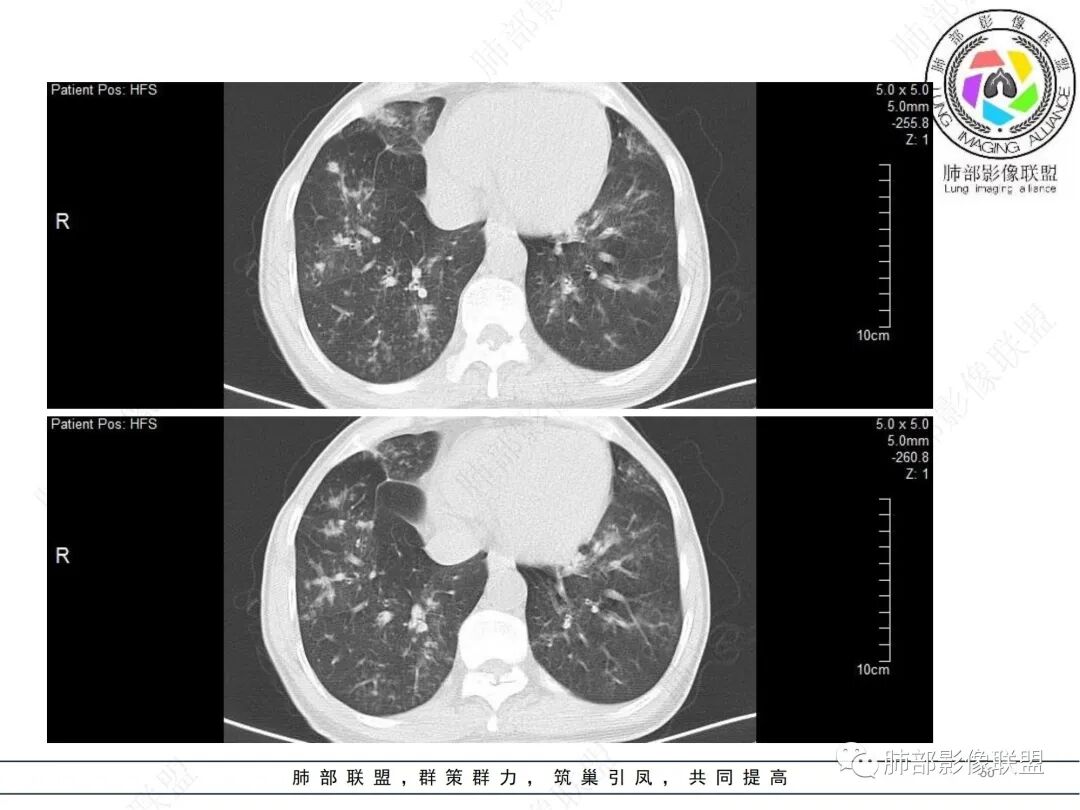

58岁男性,咳嗽胸闷3天,咳较多褐粘液痰,无发热。有2型糖尿病病史。白细胞与中性粒细胞升高。CRP升高。鳞状上皮细胞癌抗原轻度升高。结核T细胞免疫斑点实性阳性。肺炎支原体、衣原体IgG轻度升高。支气管镜显示支气管炎性改变、右肺下叶背段管腔狭窄。2.影像特点:

2022.6.24CT显示两肺弥漫性段、亚段支气管壁增厚(两肺各叶都累及),增厚的支气管壁外可见沿着支气管分布的渗出、实变影。另外远端肺内亦可见多发树芽影、结节影,其边界欠清晰。右肺下叶基底段局部胸膜下亦可见小斑片影,边界不清。2022.6.27CT显示两肺增厚的支气管壁外的渗出实变影明显增多、范围更广。远端肺内病灶亦增多、范围增大。部分位于胸膜下的病灶可见侧向融合趋势。3.病例分析:

中老年男性,咳嗽咳痰胸闷3天就诊,急性过程。有糖尿病基础。实验室检查炎症指标明显升高。结合影像学气道密切相关,首先考虑感染性病变。

影像学病灶双肺分布,支气管广泛增厚,较少见于普通社区肺炎,而更多见于气道侵袭性曲霉病。病原学检查证实烟曲霉感染的存在。